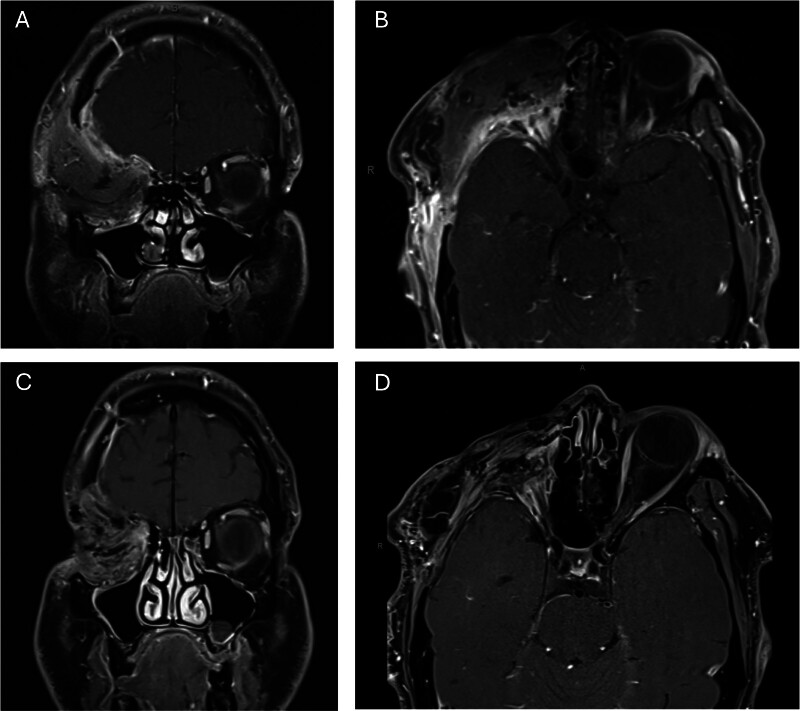

Carcinoma Ex-Pleomorphic Adenoma of the Lacrimal Gland with Intracranial Extension.

Carcinoma ex-pleomorphic adenoma (CXPA) of the lacrimal gland is rare, and its management can be complex given its anatomic location. In this case report, we describe our approach to multidisciplinary management of a CXPA with intracranial extension.